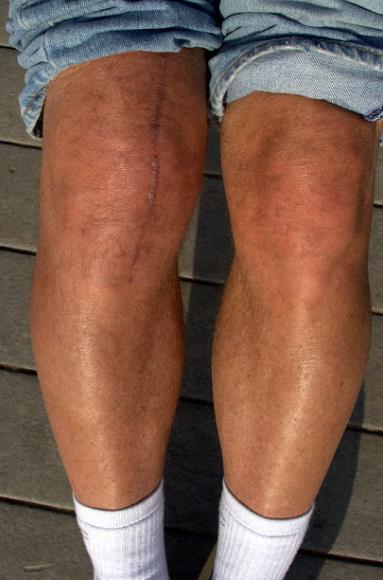

1. 퇴행성 관절염

병원을 찾는 환자들 중에 약 10~15%는 퇴행성관절염을 진단 받는다고 하는데요, 관절을 감싸고 있는 연골이 나이가 들어감에 따라 노화하거나 혹은 너무 많은 사용으로 손실이 생겨 발생하는 질환이라고 생각하면 됩니다.

평소 앉았다 일어날 때, 또 계단을 오를 때, 도보를 걸을 때 드드득, 혹은 드르륵 하면서 마치 뼈가 갈리는 듯한 소리가 난다면 퇴행성 관절염을 우선적으로 의심해봐야 합니다. 퇴행성 관절염에는 다리가 무겁게 느껴지거나, 무릎 아랫쪽 다리를 올리기 힘들다거나, 무릎 뒤쪽편이 당기는 증상도 있으니 참고하시면 좋을거 같습니다.

노화로 인해 생기는 경우가 많긴 하지만, 무릎쪽에 너무 무리를 줄 수 있는 과체중, 비만. 또 운동선수 같이 높은 강도의 훈련으로 인한 충격으로도 발생할 수 있기 때문에 꼭 나이 때문이라고 볼 수는 없습니다.